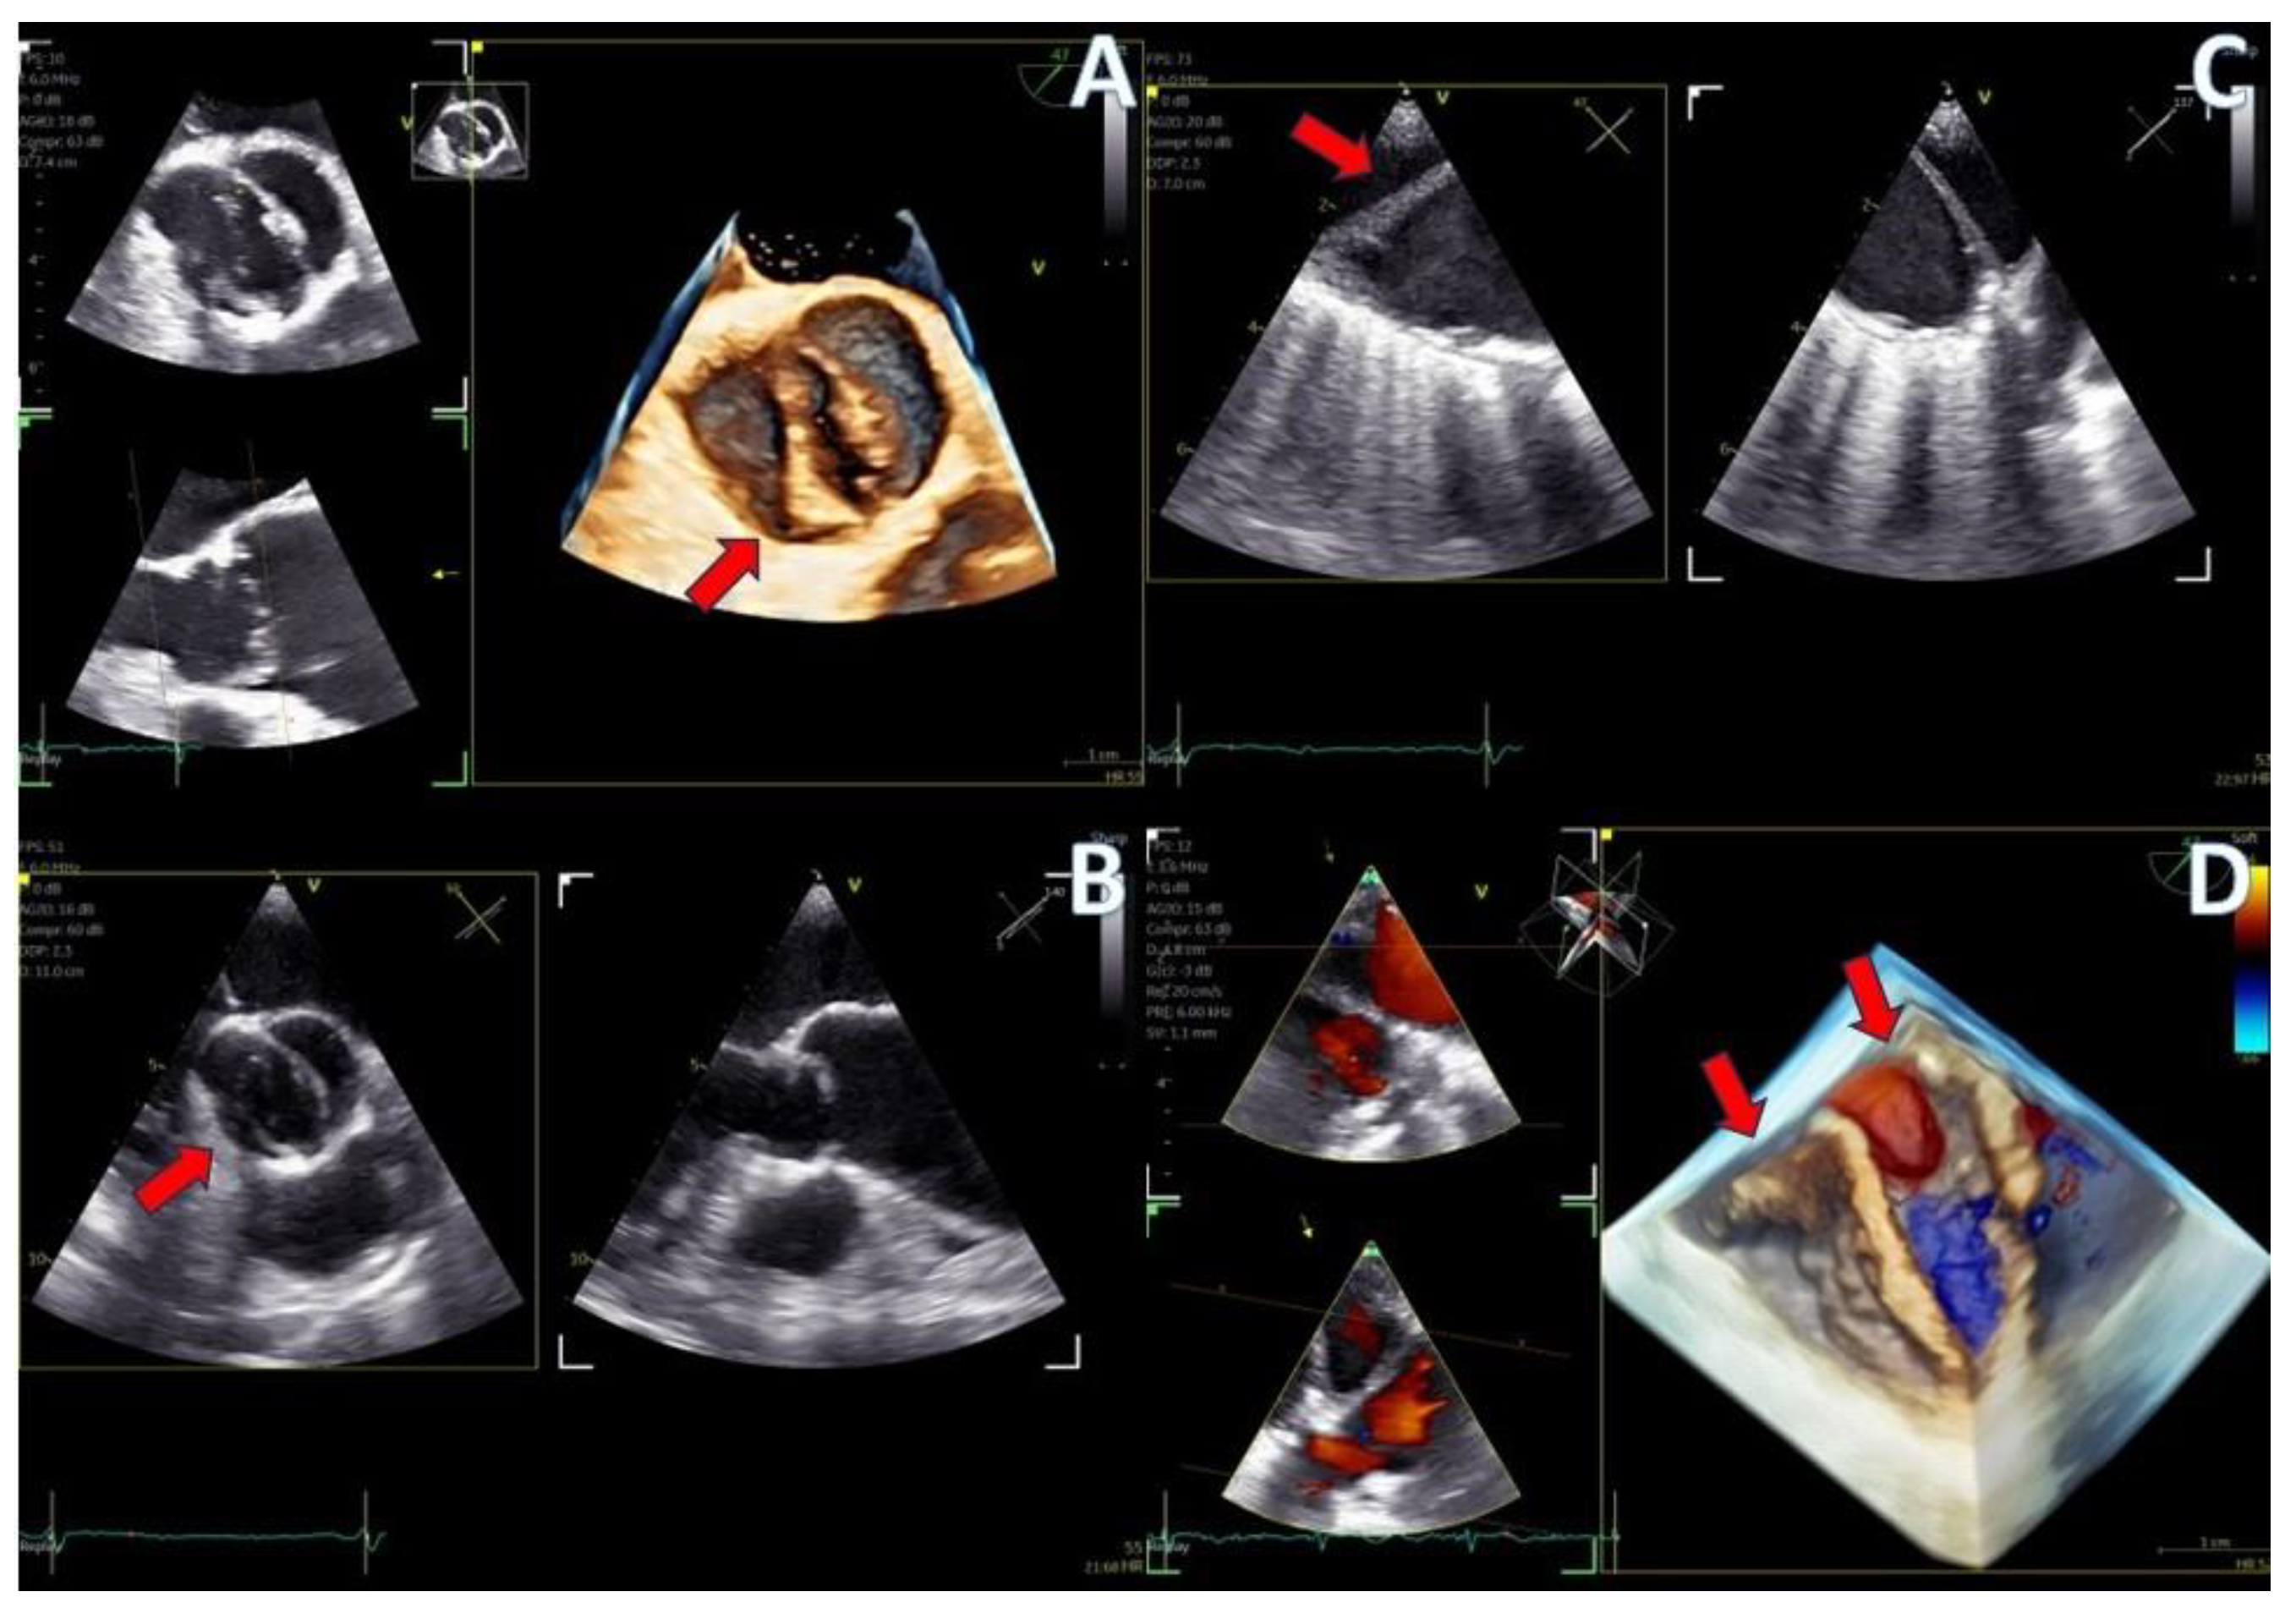

Regarding imaging quality, almost all patients exhibited excellent images without any compromise in resolution, obviating the need to confirm findings using the standard TEE probe (Figure 3 and Figure 4, video S5). Despite the one patient requiring additional sedation due to intense pharyngeal reflex, the quality of images obtained remained consistent across all cases. In 22 cases out of 30 included in this study, the 2D and 3D imaging quality received a score of 5 suggesting excellent imaging totally equal to the one acquired with the adult probe. In four cases, 2D and 3D images were commented as good with a score of 4 and in another four cases, while the 2D images were excellent, 3D images were again mentioned to be good, almost equal to the standard probe but not exceptional enough to receive a grade of 5 (Table 3).

Figure 3.

Dual crop 3D volume-rendered atrial (left) and ventricular (right) views of normal mitral valve.

Figure 4.

(A) A 4D demonstration of a true−bicuspid aortic valve (red arrow), (B) Biplane 2D demonstration of a true−bicuspid aortic valve (red arrow), (C) Chronic dissection of descending aorta (red arrow showing the wall of the true lumen), (D) 3D volume-rendered color Doppler image showing the true (right arrow) and the false lumen (left arrow).